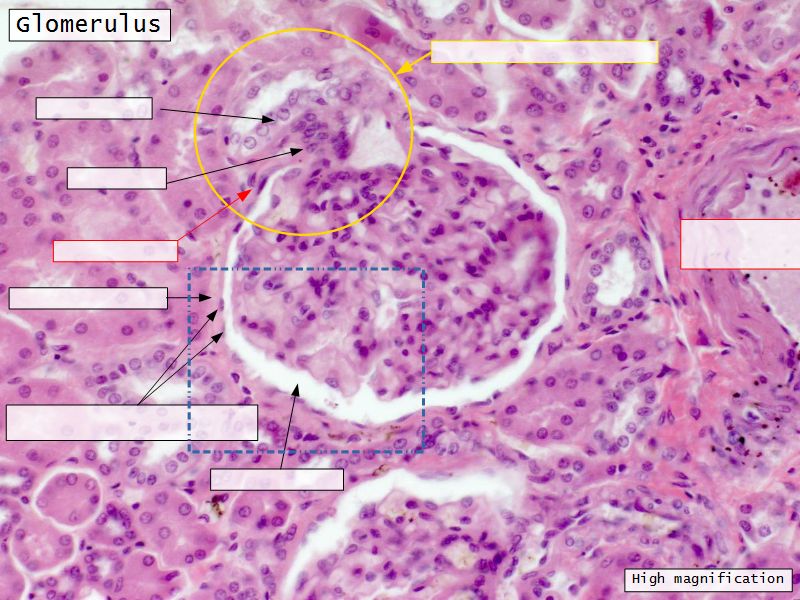

Epithelium layers

- Capillary endothelium

- Visceral layer of epithelium

- Podocytes

- Resting on glomerular basement membrane

- Capsular space

- Parietal layer of epithelium

- Simple squamous epithelium

Juxtaglomerular complex

Area where distal convoluted tubule return to glomerulus and pass through the notch between the afferent and efferent arterioles. Modification of the wall of the tubule and afferent arteriole and presence of specialised cells in the connective tissue.Modifications

- Distal convoluted tubule

- Macula densa

- Narrow epithelial cells

- Nuclei densely packed

- CT cells

- Laci cells

- Similar to mesangial cells

- Afferent arteriole

- Modified smooth muscle cells

- Juxtaglomerular cells

- Secretory function

Capillaries

- Supported by

- Mesangial cells

- Mesangial matrix

- Phagocytic

- Maintain basement membrane

- Remove macromolecular deposits

Mesangial cells

- Around capillary loops at vascular pole

- Phagocytic

- Maintain basement membrane

- Remove macromolecular deposits